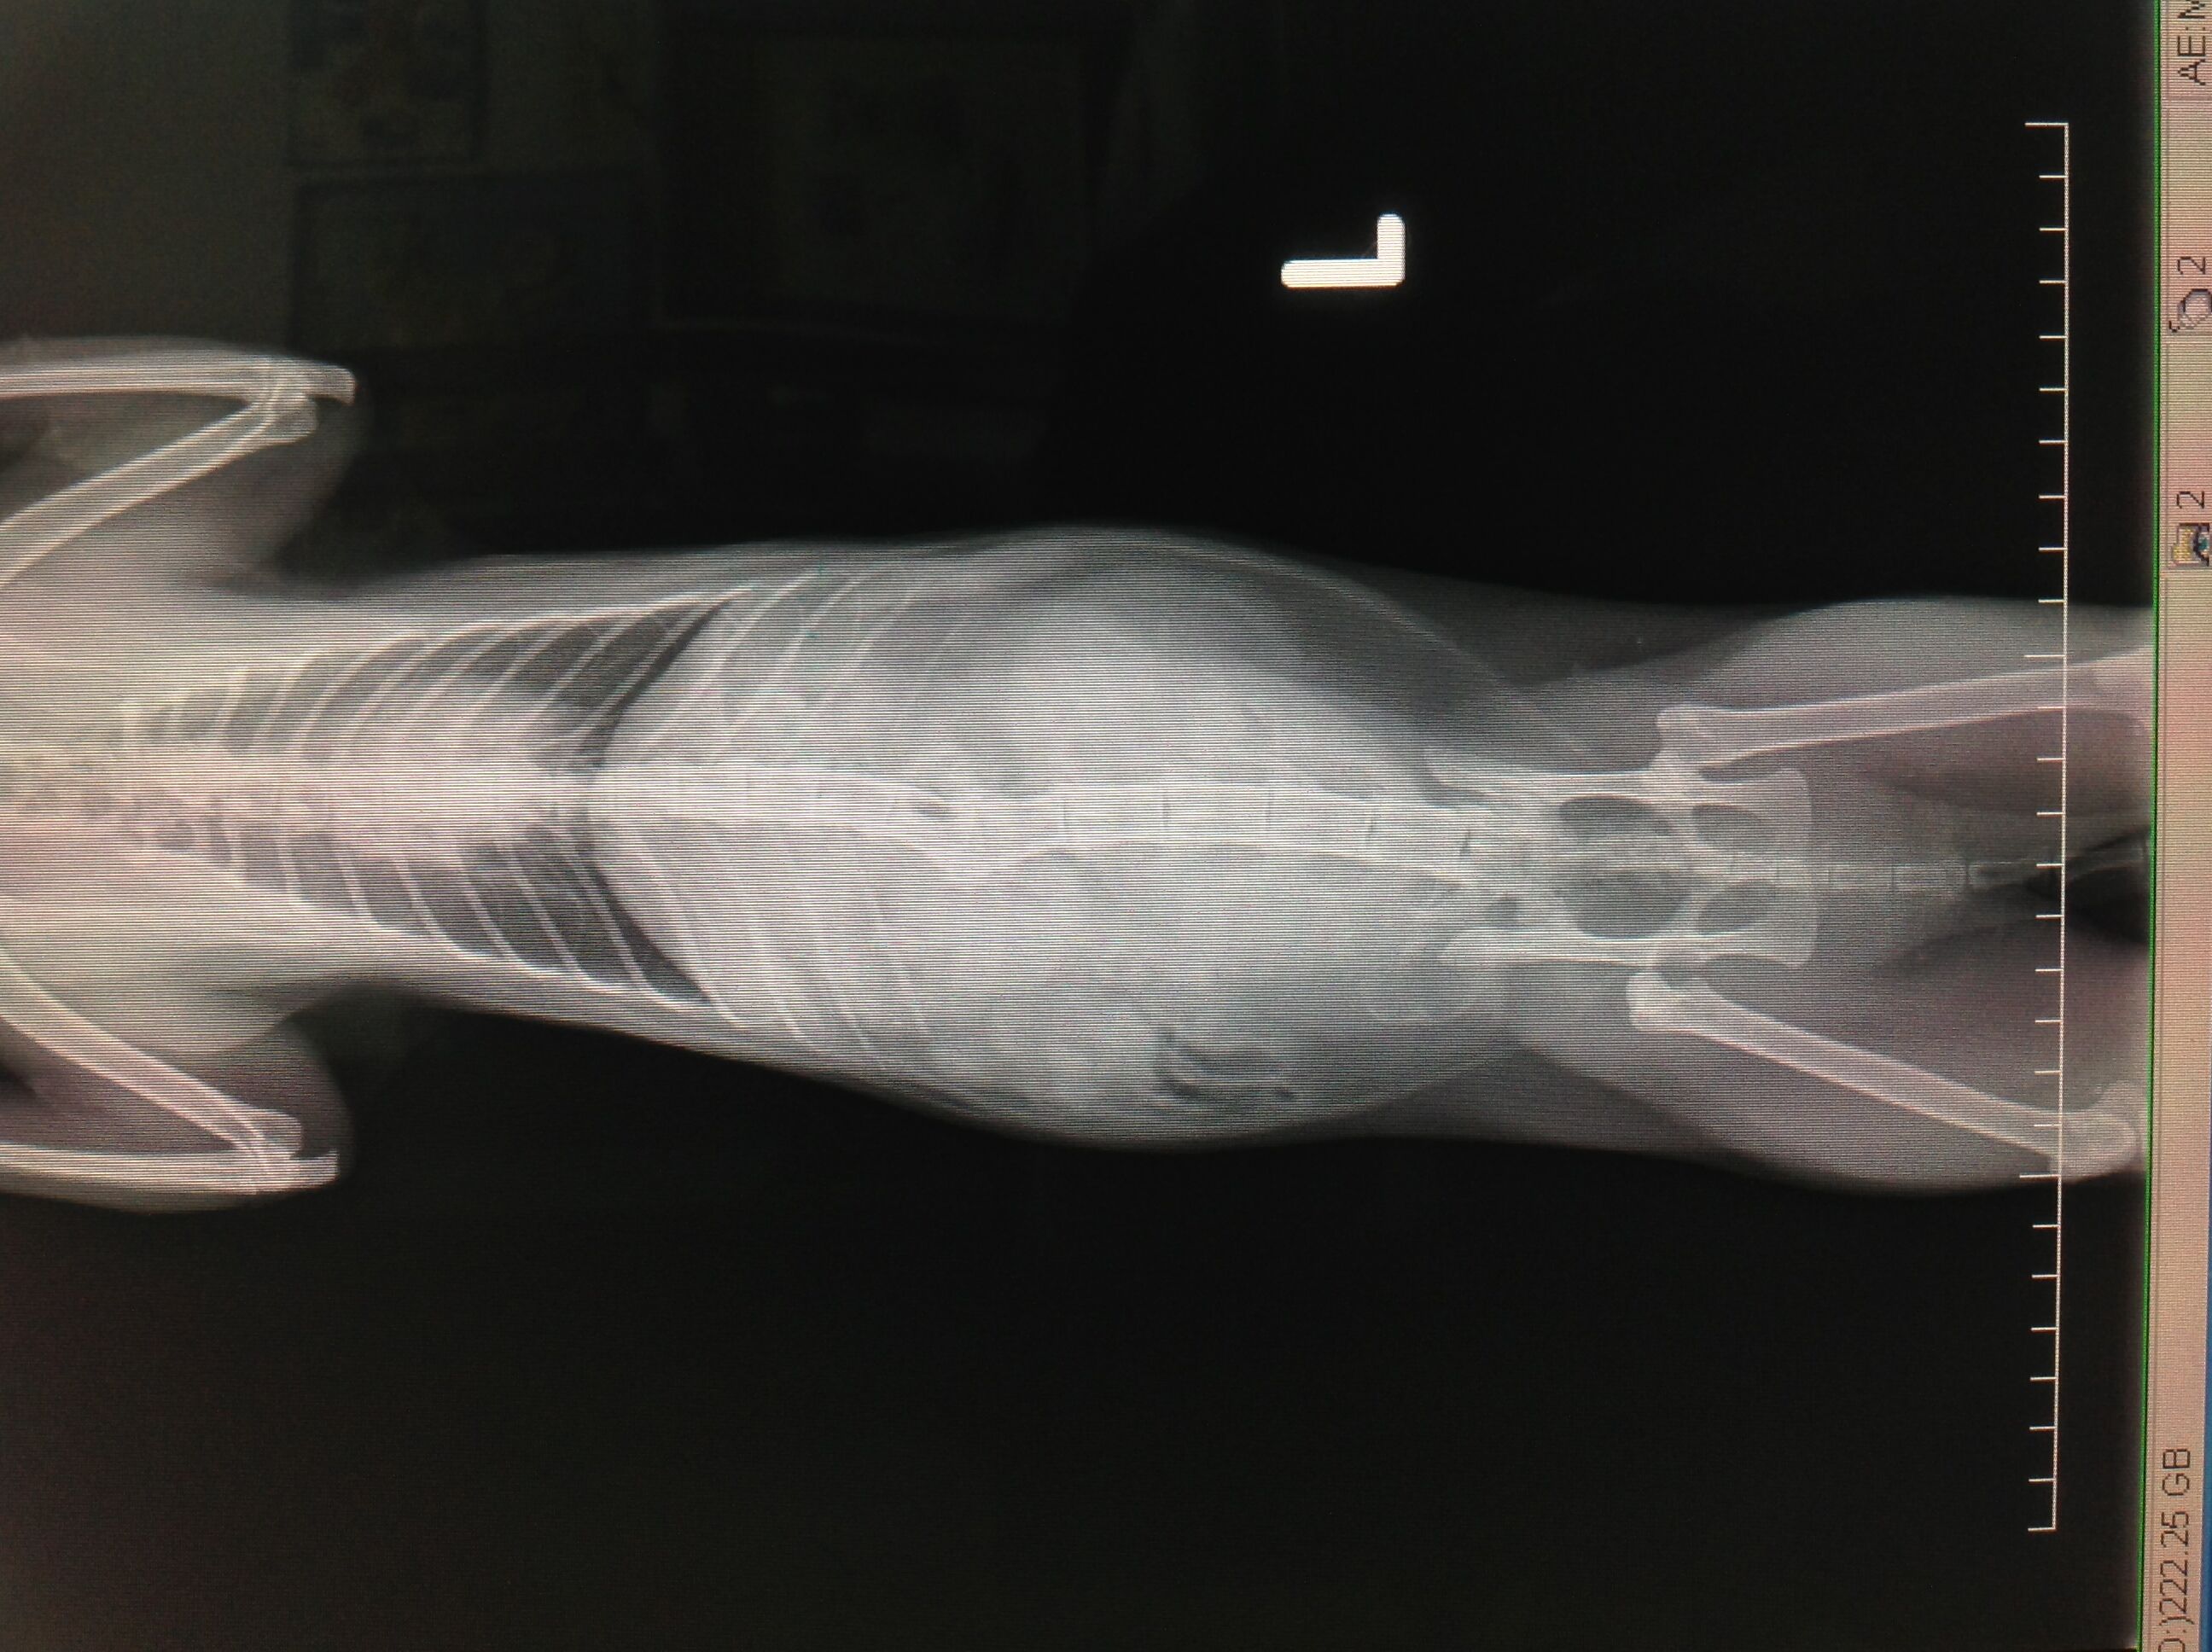

檢查發現貓咪有嚴重內出血的情形,X光片顯示貓咪懷孕了,小貓約50多天大。